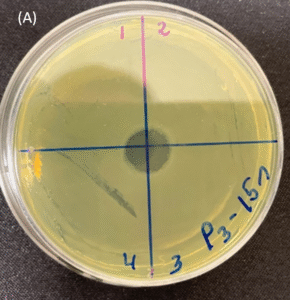

Photos of the Petri plates, 72 hours after bacterial (Pseudomonas aeruginosa) inoculation.

Image (A) shows positive bacterial growth inhibition (full translucency) at the treatment site after one dose of

UV-C for 15 seconds at 10 mm distance.

Image (B) is the control plate. The blue lines divide the plate into quadrants.